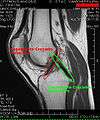

Intracapsular

The knee is stabilized by a pair of cruciate ligaments. The anterior cruciate ligament (ACL) stretches from the lateral condyle of femur to the anterior intercondylar area. The ACL is critically important because it prevents the tibia from being pushed too far anterior relative to the femur. It is often torn during twisting or bending of the knee. The posterior cruciate ligament (PCL) stretches from medial condyle of femur to the posterior intercondylar area. Injury to this ligament is uncommon but can occur as a direct result of forced trauma to the ligament. This ligament prevents posterior displacement of the tibia relative to the femur.

The transverse ligament stretches from the lateral meniscus to the medial meniscus. It passes in front of the menisci. It is divided into several strips in 10% of cases.[15] The two menisci are attached to each other anteriorly by the ligament.[17] The posterior and anterior meniscofemoral ligaments stretch from the posterior horn of the lateral meniscus to the medial femoral condyle. They pass posteriorly behind the posterior cruciate ligament. The posterior meniscofemoral ligament is more commonly present (30%); both ligaments are present less often.[15] The meniscotibial ligaments (or "coronary") stretches from inferior edges of the mensici to the periphery of the tibial plateaus.

Knee MR

Cruciate ligaments